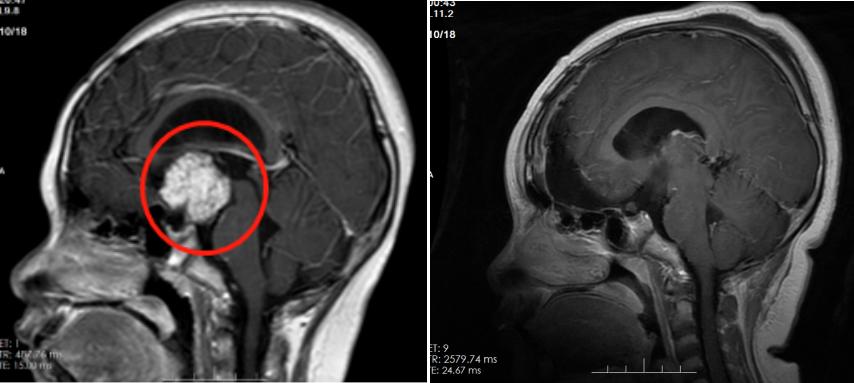

术前(左)术后(右)影像对比

结合相关病史,我院神经外二科副主任林涛怀疑是颅咽管瘤压迫垂体,导致患儿出现系列症状。“手术指征明确,建议完善相关检查,择期行手术治疗。”确定手术方案后,神经外二科团队为患者实施鞍区肿瘤切除术。

术后病理诊断为颅咽管瘤,进一步证实了林涛术前的诊断。“颅咽管瘤一般不影响孩子的生长,但如果肿瘤致下丘脑垂体受损导致内分泌紊乱,影响生长激素的分泌,是很可能会影响生长发育的。”林涛解析。